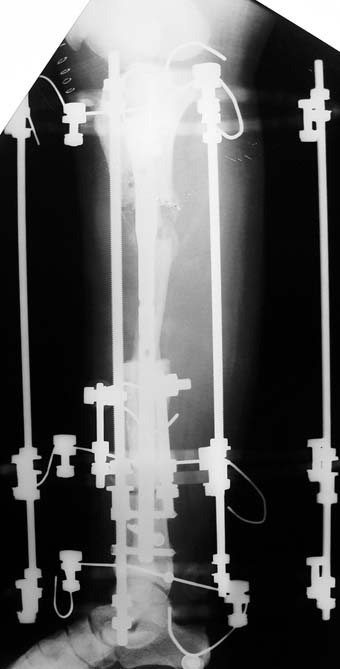

Appropriate radical debridement necessitates excision of all necrotic bone and soft tissues, and frequently causes instability at the involved extremity. The remaining bone and soft tissue defect has to be fixed and reconstructed. The distraction osteogenesis method of Ilizarov is used successfully for achievement of union, correction of the deformity, elimination of limb length inequality and reconstruction of segmental bone defects.

The duration of external fixation (external fixation index) depends on the amount of distraction required, and the extremity is prone to complications during this period. After the distraction phase is completed, the external fixator remains in place during the consolidation phase, which lasts twice as long as the distraction phase; but this period is hardly tolerated. If the external fixator is removed before sufficient consolidation is achieved, fractures, deformity and shortness will be the result. In our department, ‘lenghthening over nail’ method is used in order to decrease the external fixation index and increase patient comfort and activity level. In this method, the intramedullary nail is statically locked after the completion of the distraction phase, and external fixator is removed. The extremity is stabilized by the intramedullary nail during consolidation phase. In this way, complications due to long external fixation index or early removal of the external fixator are avoided.